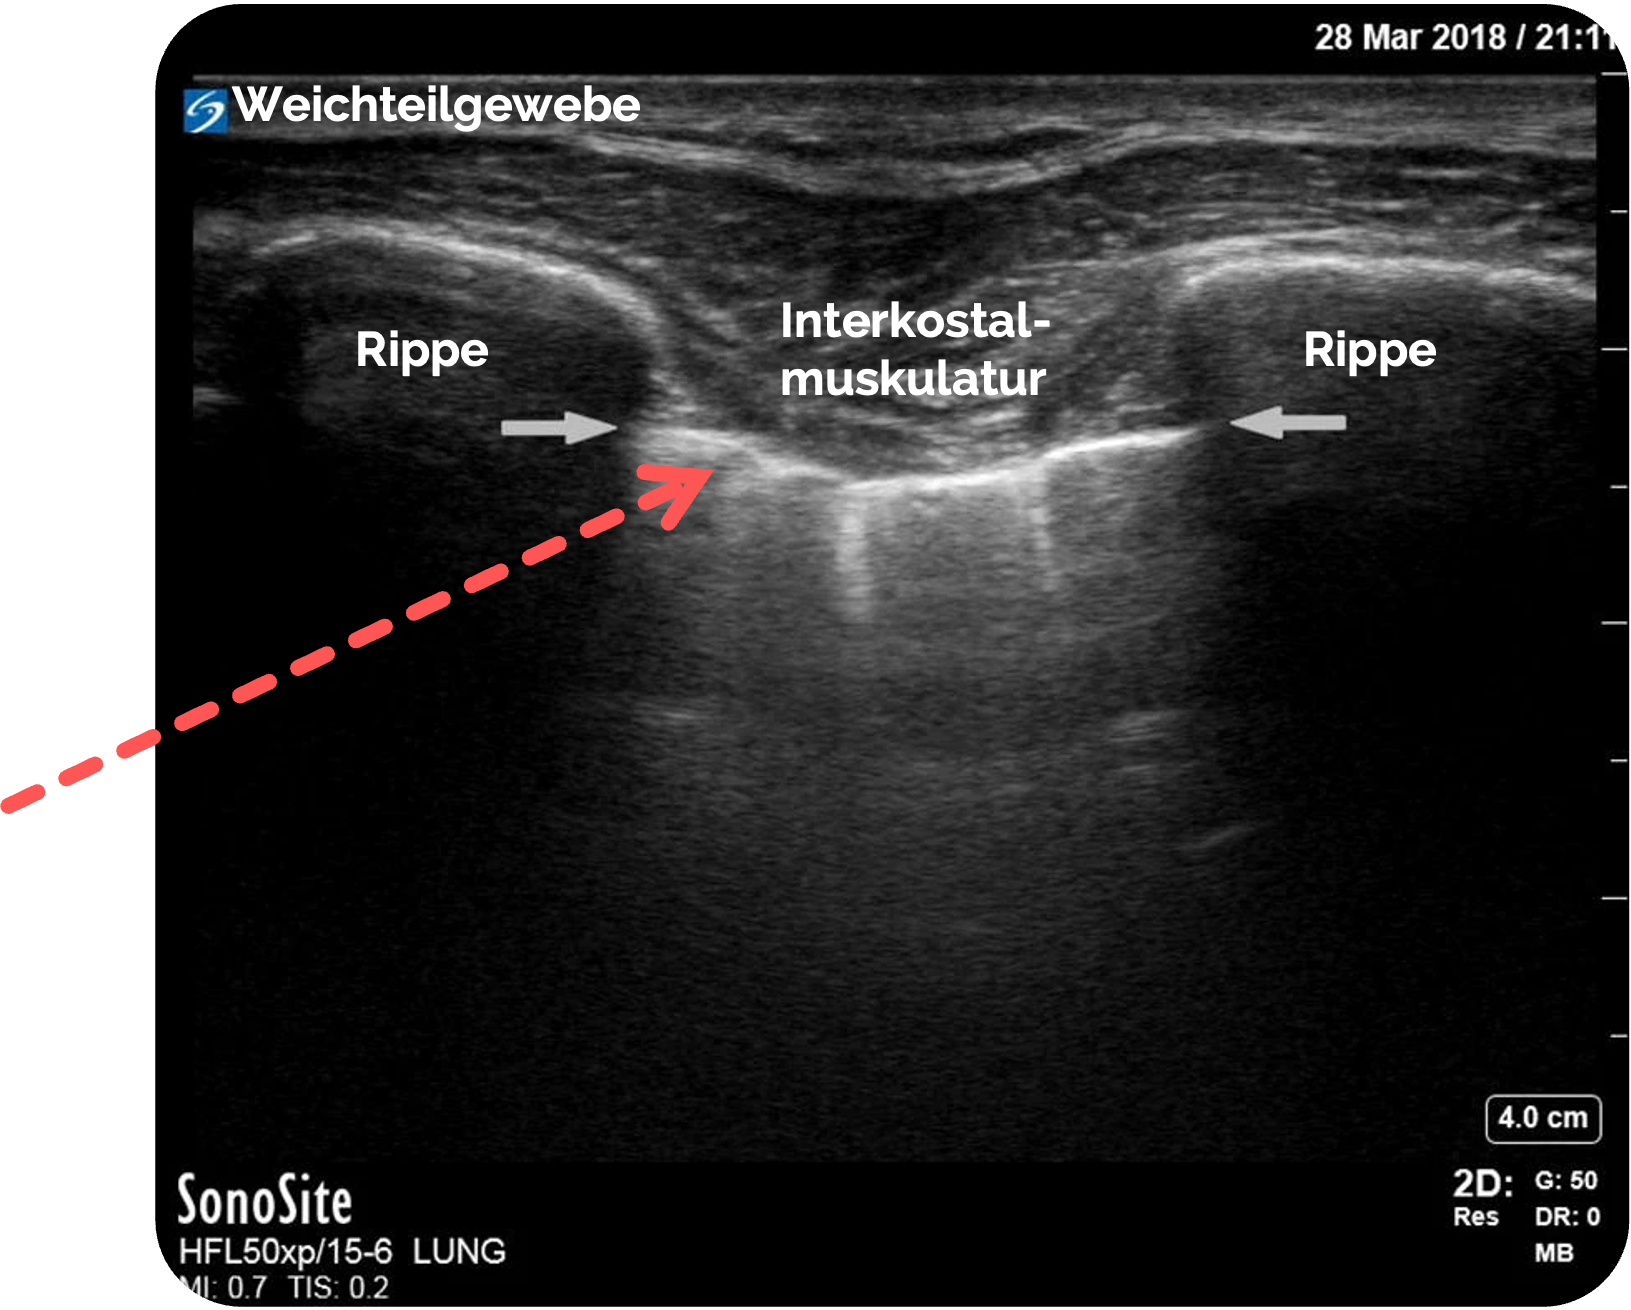

Schritt 2: Anatomische Leitstrukturen - Orientierung

- Oberflächliches Weichteilgewebe und Interkostalmuskulatur

- Rippen

beidseits rechts und links als echoreiche, gebogene Konturen mit Schattenbildung - Dazwischen die Pleuralinie als glatte, echoreiche horizontale Linie (siehe roter Pfeil)

Figure 1 aus Ketelaars, R., Reijnders, G., van Geffen, GJ. et al. ABCDE of prehospital ultrasonography: a narrative review. Crit Ultrasound J 10, 17 (2018). https://doi.org/10.1186/s13089-018-0099-y. Teilausschnitt des Originalbilds. Es wurden die Beschriftungen und der rote Pfeil hinzugefügt.